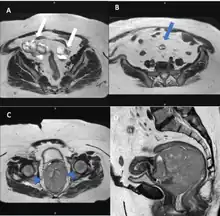

Magnetic resonance imaging

Pelvic MRI images. A: Axial T2-weighted image shows multicystic neoplastic masses (white arrows) with solid components in both ovaries. B: A peritoneal implant (blue arrow) with similar characteristics to the ovarian lesions is seen in the peritoneal cavity. C and D: T2-weighted images of the uterine cervix in the axial and sagittal plane reveal the bulky cervical tumor. The cervical stromal ring is well preserved (arrowhead)[18]

Although magnetic resonance (MRI) scans are not commonly employed for ovarian cancer detection, the majority of ultrasound-detected ovarian masses are usually benign. The combined approach of ultrasound with Doppler, along with the selective use of contrast-enhanced MRI, proves to be an efficient diagnostic method for identifying benign adnexal masses with distinctive features, including functional masses, dermoid, endometrioma, fibroma, pedunculated fibroid, hydrosalpinx, and peritoneal inclusion cysts.[19] This integrated diagnostic strategy is effective in preventing unnecessary surgical intervention. Additionally, the use of MRI contributes to a decrease in false-positive diagnoses, ultimately reducing the overall number of unnecessary surgical procedures related to ovarian masses.